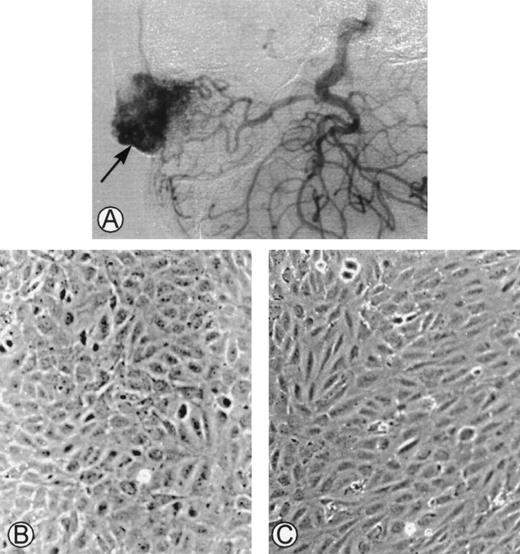

This study was conducted in accordance with the principles of the Declaration of Helsinki and the 1975 Declaration of Tokyo. Surgical excisions were performed in 11 consecutive patients with arteriovenous malformations, and samples were collected (Fig1A). Cells were successfully cultured from the surgical biopsies of 6 patients. Because a limited number of cells grew in culture, a complete characterization could only be achieved in 4 cases. In the other 5 cases, the tissues were either necrotic after embolization, infected, or did not grow in in vitro conditions. The main clinical features of the patients are summarized in Table1. The hemostatic parameters were normal and there was no evidence of intravascular coagulation.

(A) Angiogram of one of the cephalic arteriovenous malformations. The vascular tumor was embolized using an endovascular technique and was operated on. The specimen was used as starting material to obtain endothelial cells derived from the malformation. (B) Phase-contrast microphotographs of confluent HUVEC or (C) confluent AMEC grown on gelatin-coated plastic dishes (original magnification ×100).

The initial culture from surgical pieces of arteriovenous malformations (Fig 1A) contained heterogeneous populations. Only cultured cells that had the morphological characteristics of endothelial cells were kept. At confluence, HUVEC had a cobblestone aspect when cultured on gelatin-coated plastic dishes with a strict monolayer growth (Fig 1B). At confluence, AMEC cultured on gelatin-coated plastic dishes had an elongated form with an endothelial-like polygonal morphology. They were closely contiguous and grew as a monolayer (Fig 1C).